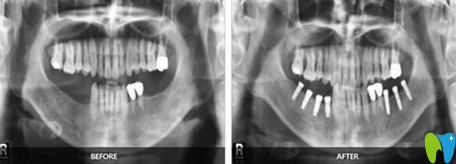

牙齒種植】:

顧客評價:爸爸在這里做的即刻種植,技術(shù)挺不錯的,種植完牙齒當(dāng)天就能吃飯,剛開始我還擔(dān)心老年人不好恢復(fù),沒想到恢復(fù)也挺不錯的,而且老爸現(xiàn)在胃口挺好的,胃口好了心情也不錯,挺適合老年人的。

福州貝臣齒科種植牙案例